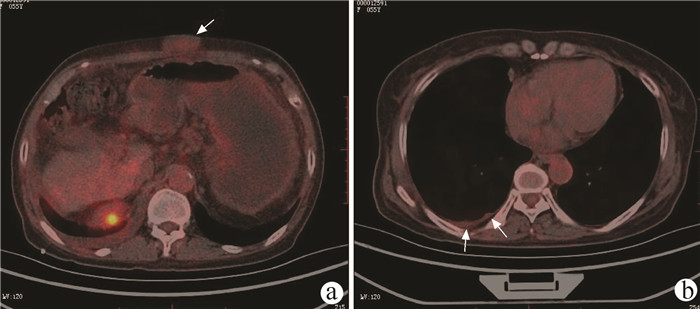

经皮冷冻消融联合无水酒精注射治疗70岁以上老年肝细胞癌患者的效果及安全性分析

罗婧, 吕采红, 杨永平

2022, 38(2): 365-371. DOI: 10.3969/j.issn.1001-5256.2022.02.021

摘要(965) HTML (363) PDF (2738KB)(61)

摘要:

目的  探讨经皮冷冻消融(CRYO)联合无水酒精注射(PEI)对早期老年肝细胞癌患者的疗效和安全性。  方法  回顾性纳入解放军总医院第五医学中心2014年1月—2018年1月收治的92例老年肝细胞癌患者,其中单一CRYO治疗组46例,CRYO联合PEI(联合治疗)组46例。比较两种治疗方式的效果,不良反应及治疗前后肝功能相关指标的变化,并随访患者肿瘤的复发及生存预后情况。正态分布的计量资料两组间比较用t检验;非正态分布的计量资料两组间比较采用Mann-Whitney U秩和检验。计数资料两组间比较采用χ2检验。两组的生存时间采用Kaplan-Meier方法进行生存分析,并用log-rank检验生存曲线的差异;通过Cox回归法确定影响生存预后的独立危险因素。  结果  联合治疗组和CRYO组初次消融的有效率分别为89.1%和73.9%,组间差异无统计学意义(P>0.05)。CRYO组和联合治疗组患者术后总生存率和无瘤生存率间的差异均无统计学意义(P值均>0.05),但联合治疗组患者术后第1、2和3年局部肿瘤进展率分别为20%、21%和21%,明显低于CRYO组的30%、46%、46%(χ2=4.187,P<0.05)。多因素Cox回归分析提示行单一CRYO治疗可能是局部肿瘤进展率的独立危险因素(HR=2.206,95%CI: 1.003~4.850, P=0.049)。在不良反应的发生率上两组间差异没有统计学意义(P>0.05),但CRYO组有3例严重不良反应,联合治疗组未出现严重不良反应。  结论  对于早期老年肝细胞癌患者,CRYO联合PEI治疗较单纯CRYO治疗安全有效,能明显降低局部肿瘤进展率。